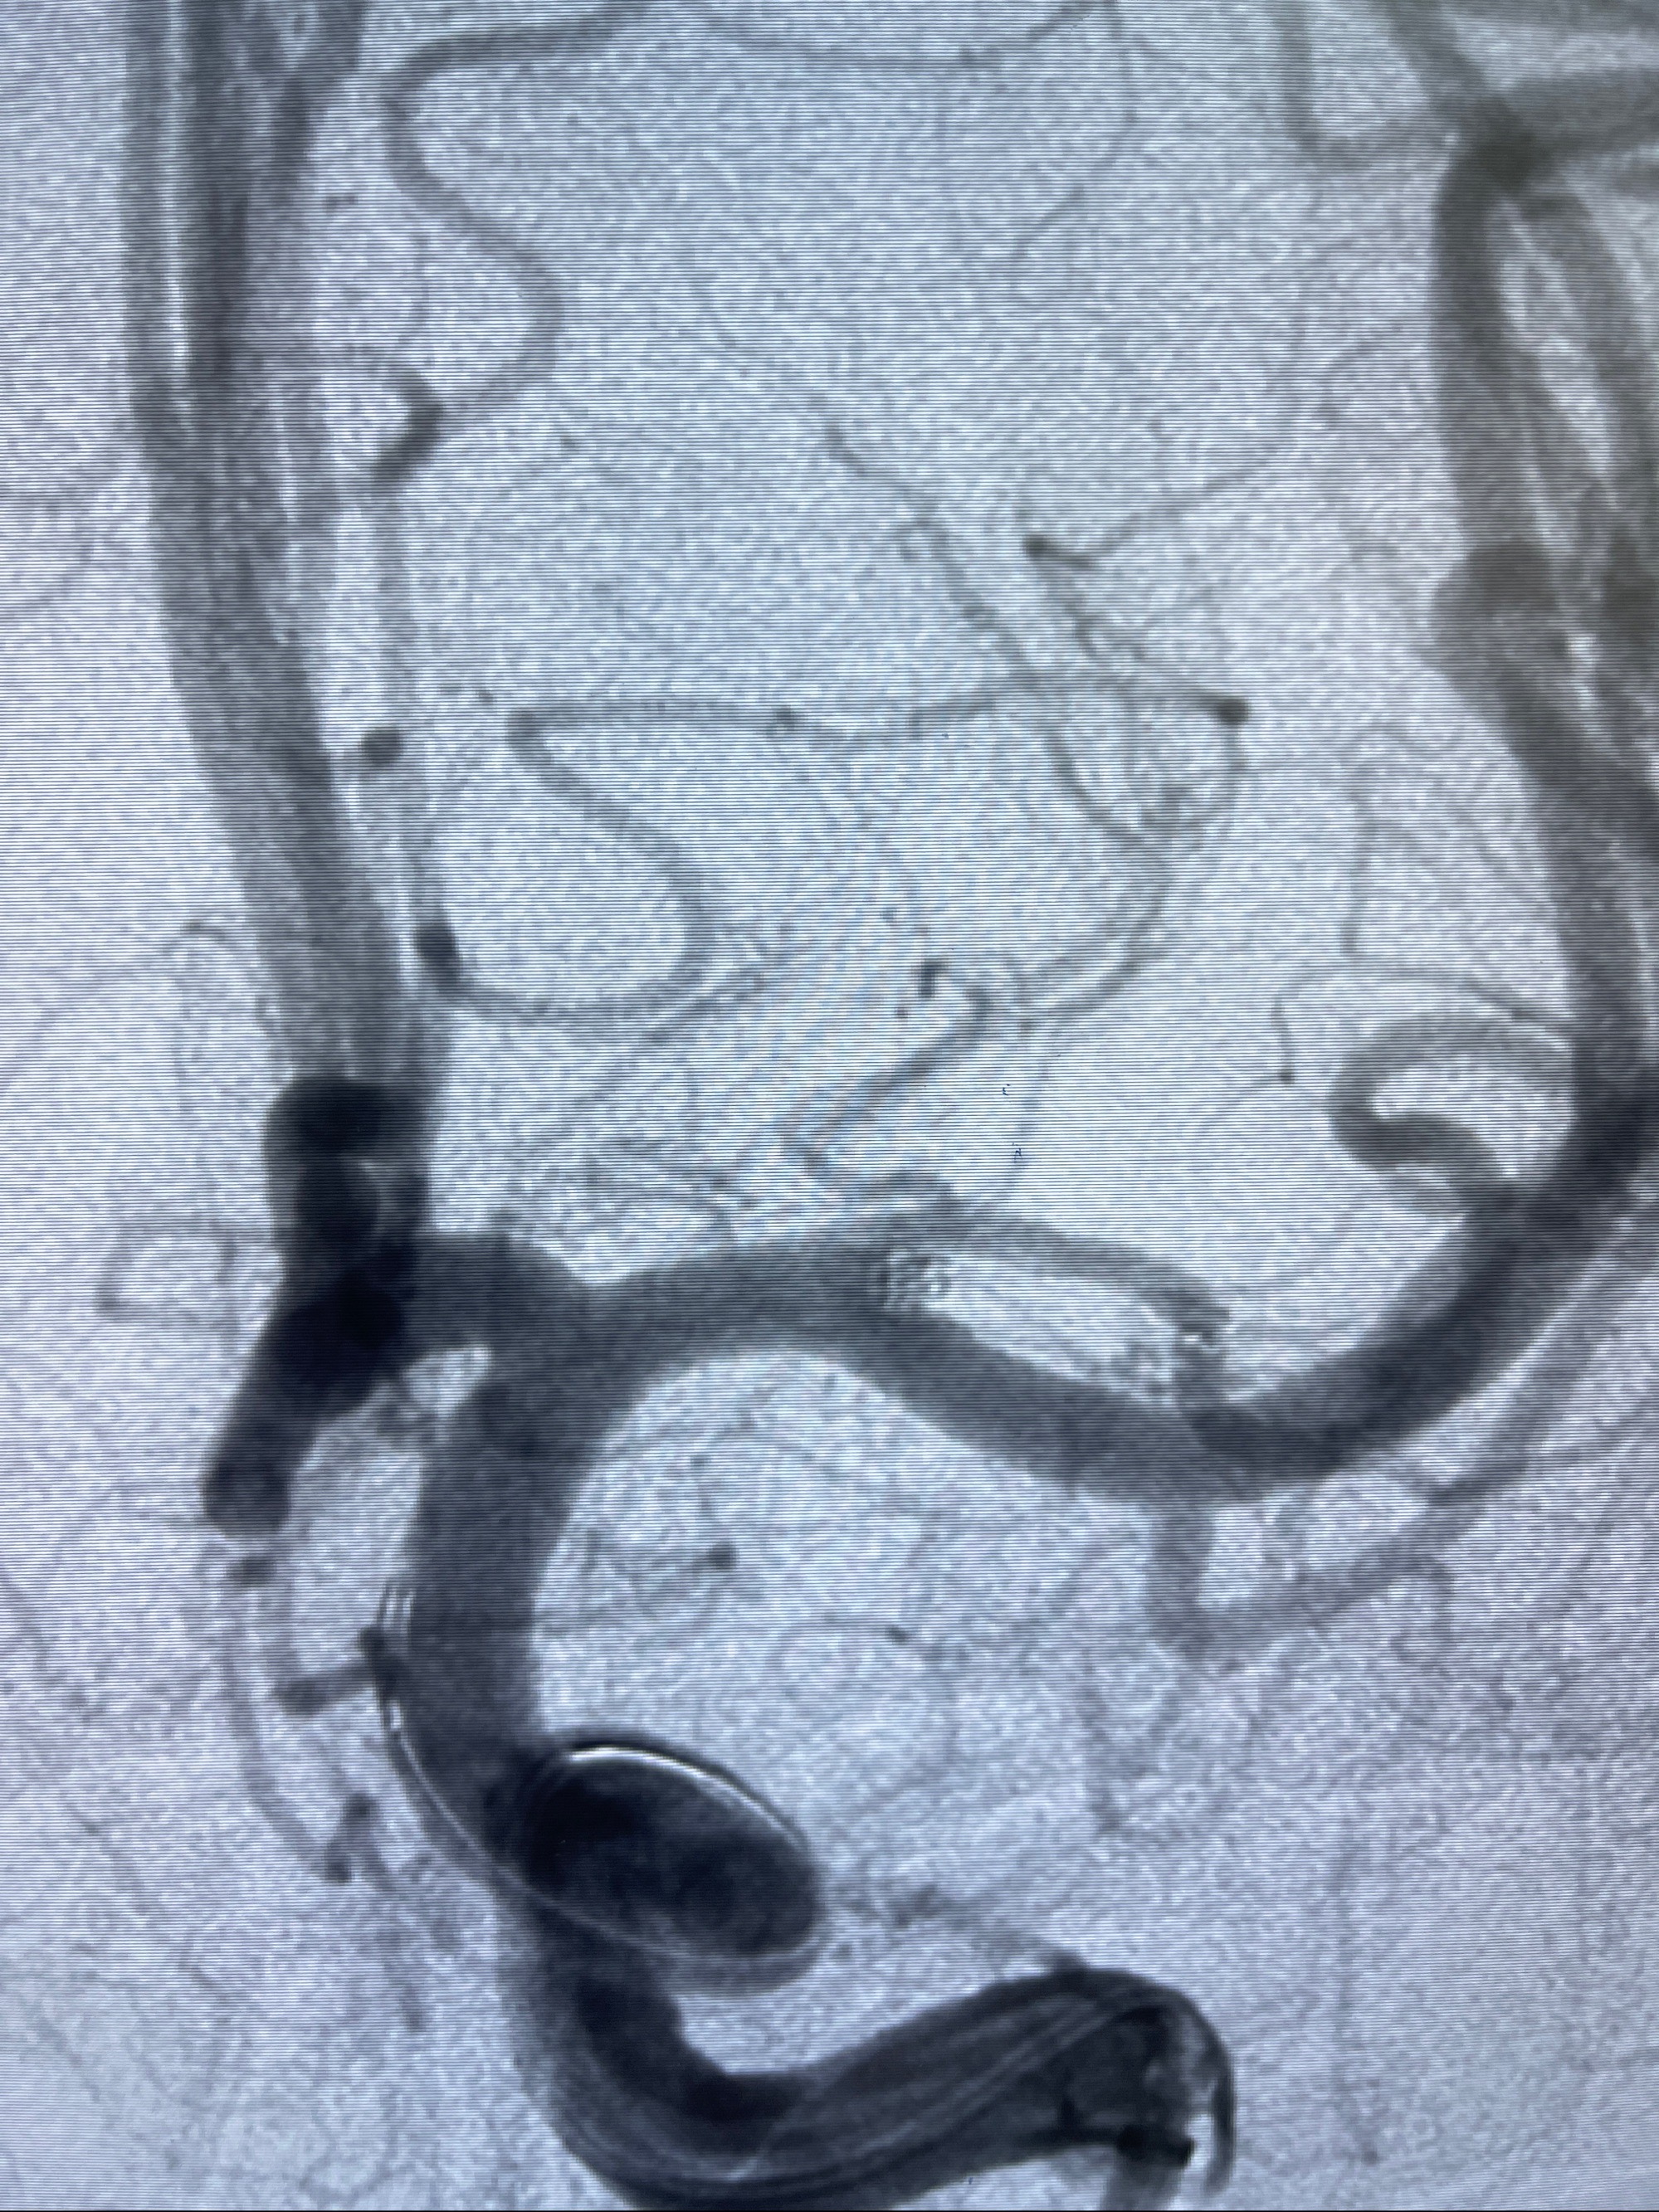

2023-08-14DSA:

左侧大脑中动脉动脉瘤,约2.6-2.8-3.4-2mm大小(瘤颈部、瘤体部、瘤高)

1.左侧大脑中动脉动脉瘤,约2.6-2.8-3.4-2mm大小(瘤颈部、瘤体部、瘤高)